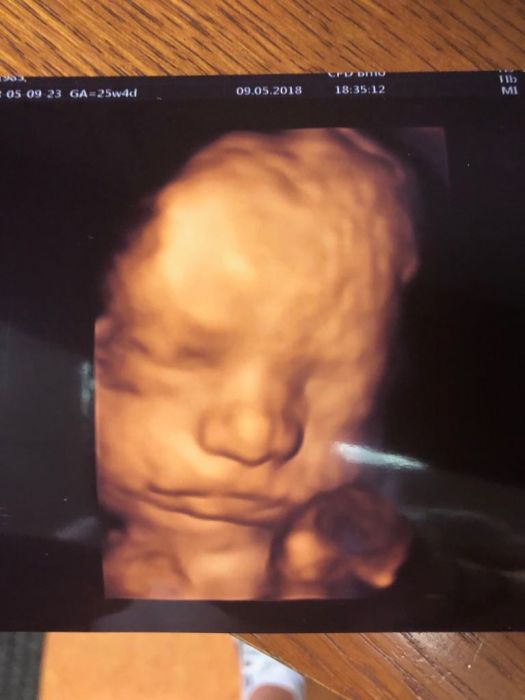

A holky co takhle nějaké utz fotky miminek? :) ja pridávám 4D Jonáše. Doktor si na posledni kontrole sam vzpomněl ze minule moc nespolupracoval a udělal mi ještě jednu hezkou fotku.

Test na cukrovku ok. Rikal, ze me ceka nejdulezitejsi a nejvic nebezpecny mesic, at jsem opatrna. Fotecku taky poslu :-)